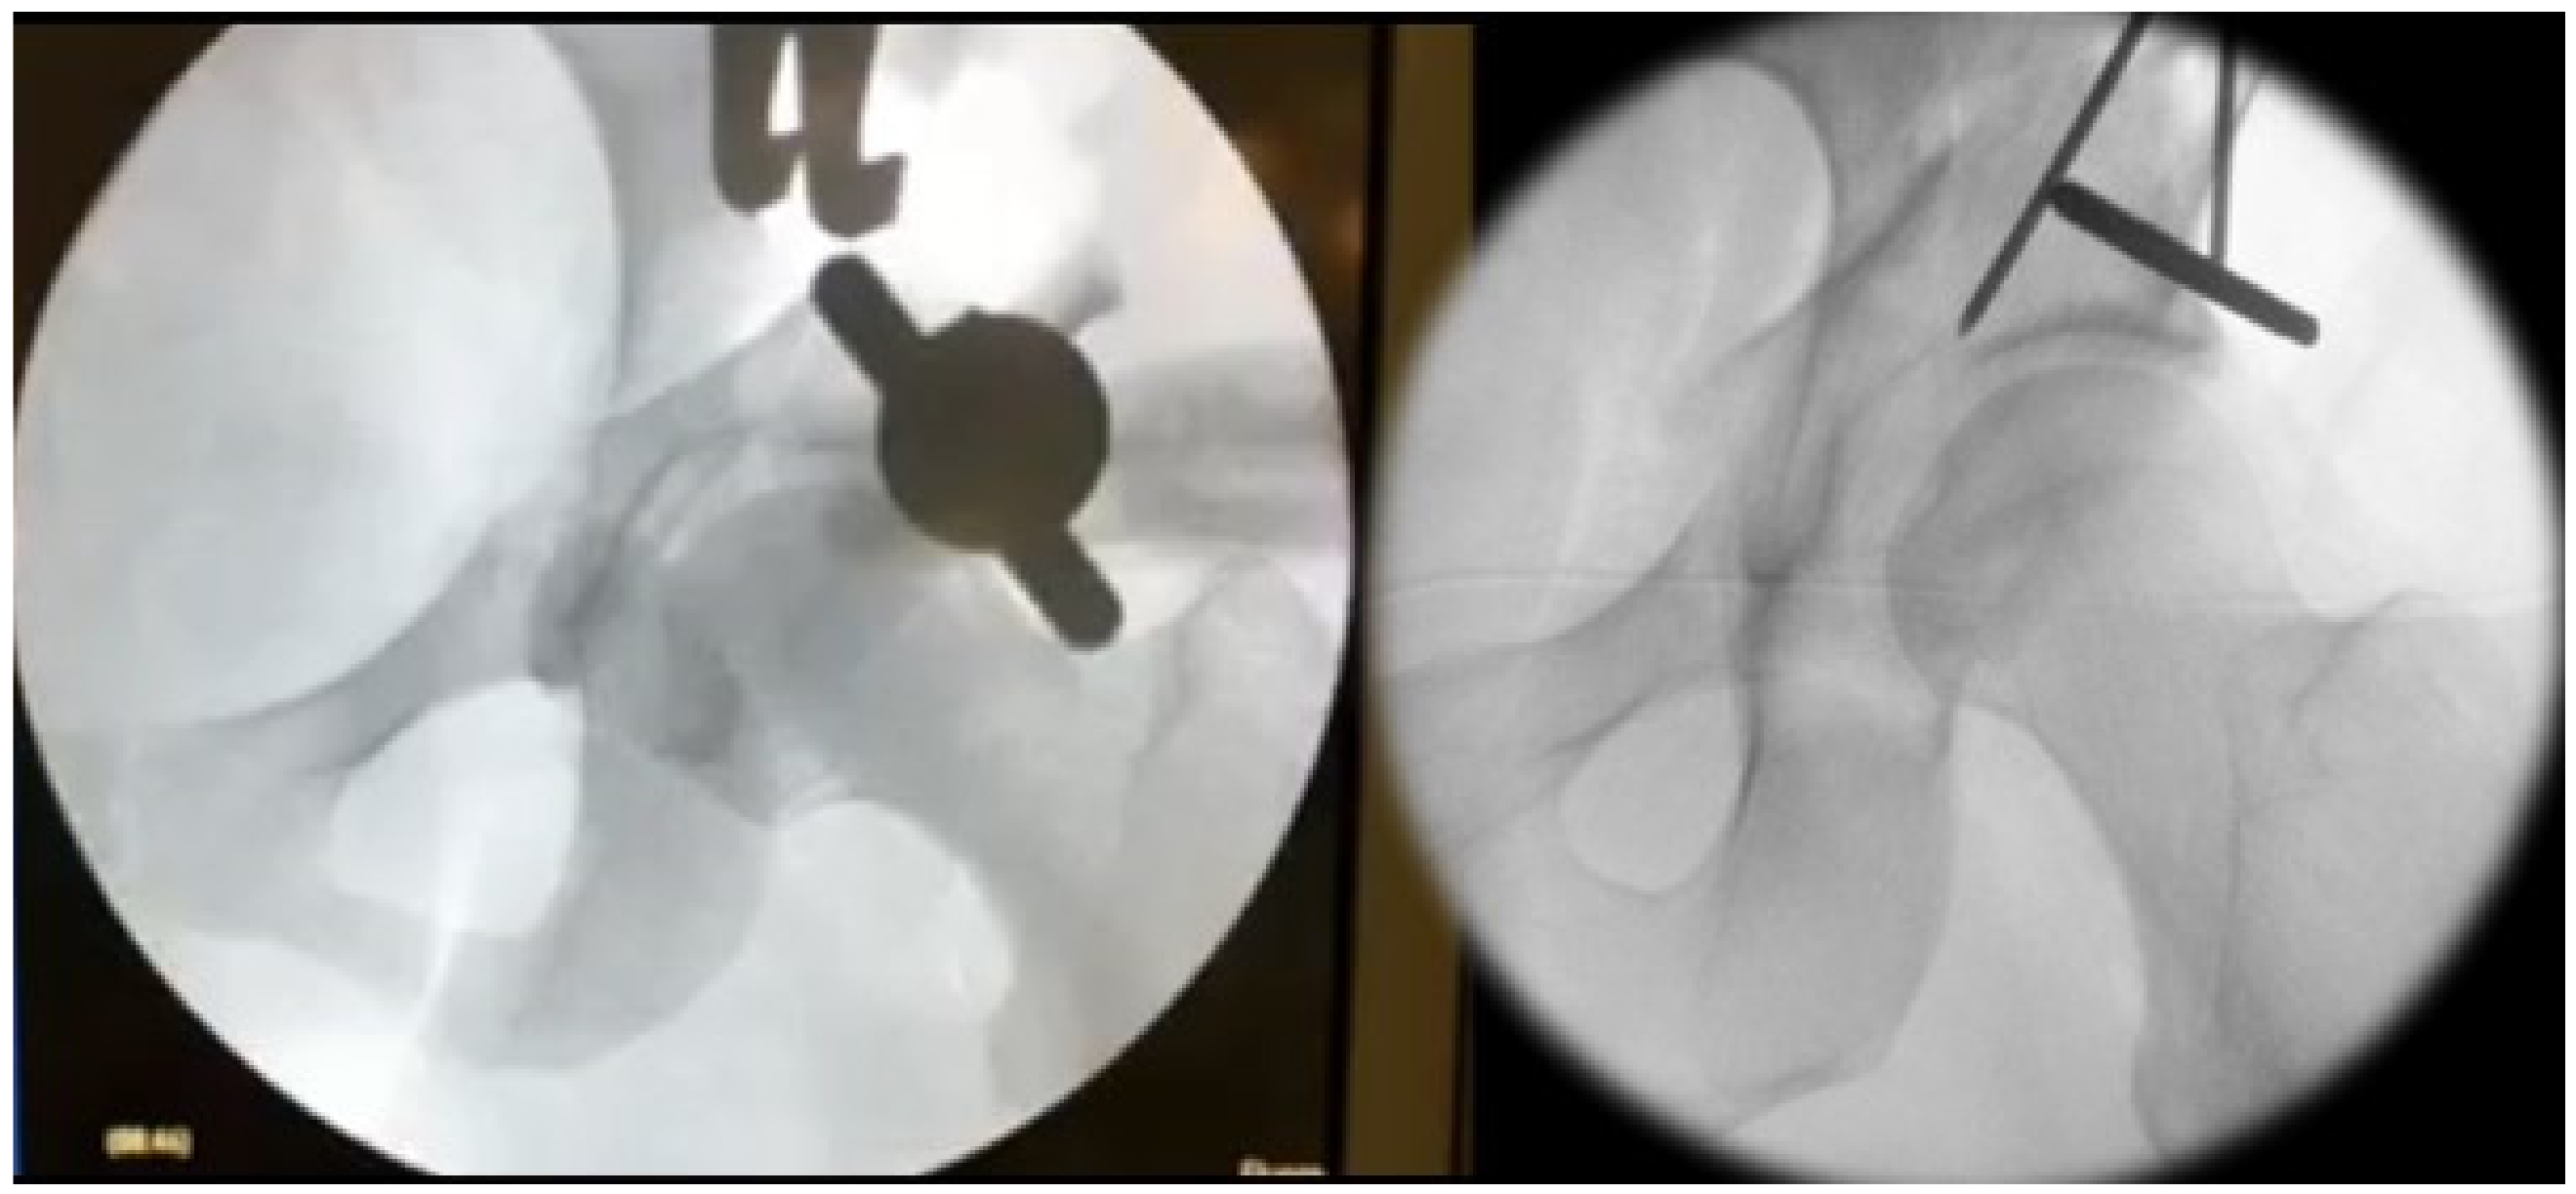

2.3. Surgical Technique